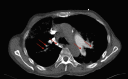

An Audaciously Aneurysmal Atrium